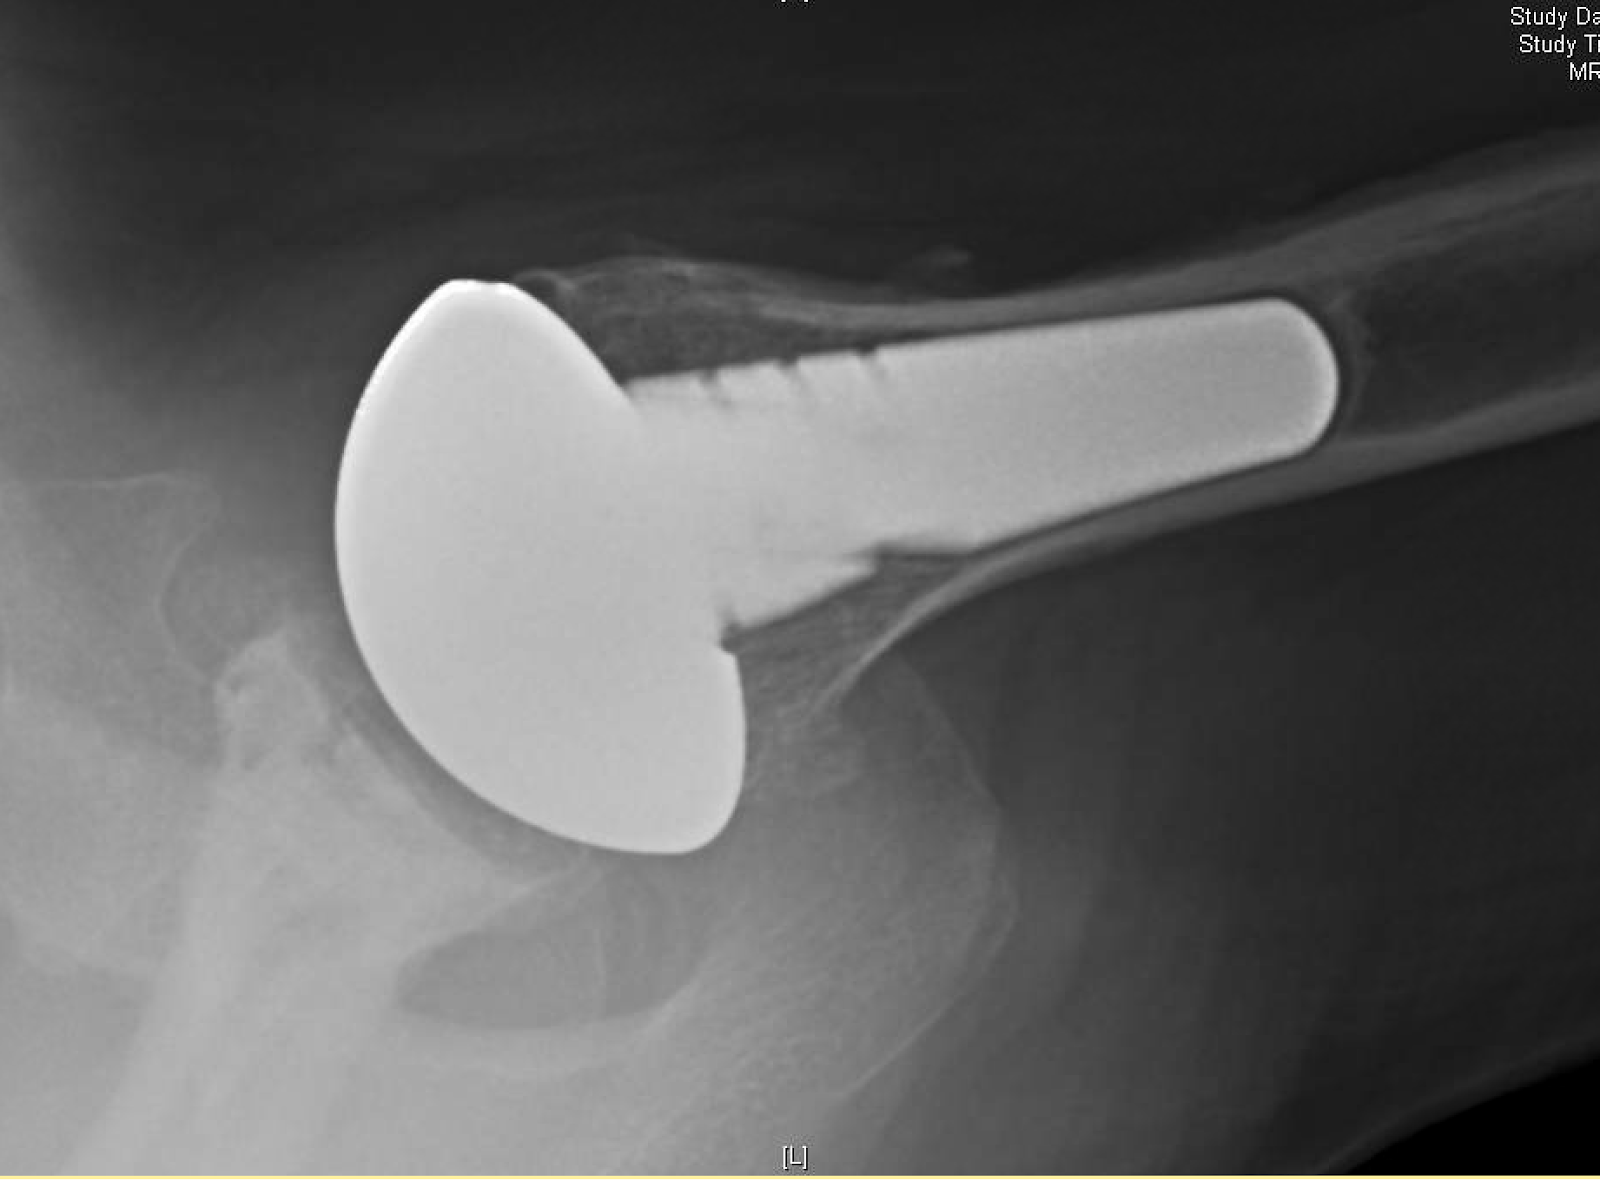

Shoulder Arthritis / Rotator Cuff Tears / Shoulder Pain Rotator Cuff Surgery Infection the outcomes after arthroscopic rotator cuff repair (rcr) have been reported to be successful. However, more than 50% of patients may require. deep infection after rcr can be treated with open or arthroscopic debridement. The incidence of deep infections (defined as an. the role of c acnes causing postoperative infection following shoulder surgery is being increasingly recognized.. Rotator Cuff Surgery Infection.

Shoulder Arthritis / Rotator Cuff Tears / Shoulder Pain Total Rotator Cuff Surgery Infection The incidence of deep infections (defined as an. the role of c acnes causing postoperative infection following shoulder surgery is being increasingly recognized. However, more than 50% of patients may require. the incidence of infection after rotator cuff repair and shoulder arthroplasty ranges from 0.27 to 1.9 % and. deep infection after rcr can be treated with. Rotator Cuff Surgery Infection.

Shoulder Arthritis/Joint Replacement Rotator cuff tears Single stage Rotator Cuff Surgery Infection the incidence of infection after rotator cuff repair and shoulder arthroplasty ranges from 0.27 to 1.9 % and. The incidence of deep infections (defined as an. However, more than 50% of patients may require. the outcomes after arthroscopic rotator cuff repair (rcr) have been reported to be successful. propionibacterium acnes has been implicated as a cause of. Rotator Cuff Surgery Infection.